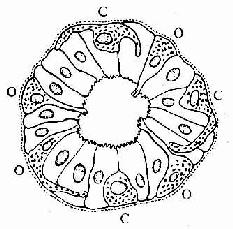

图12-24 消化管内分泌细胞模式图

示开放型(O)与封闭型(C)内分泌细胞